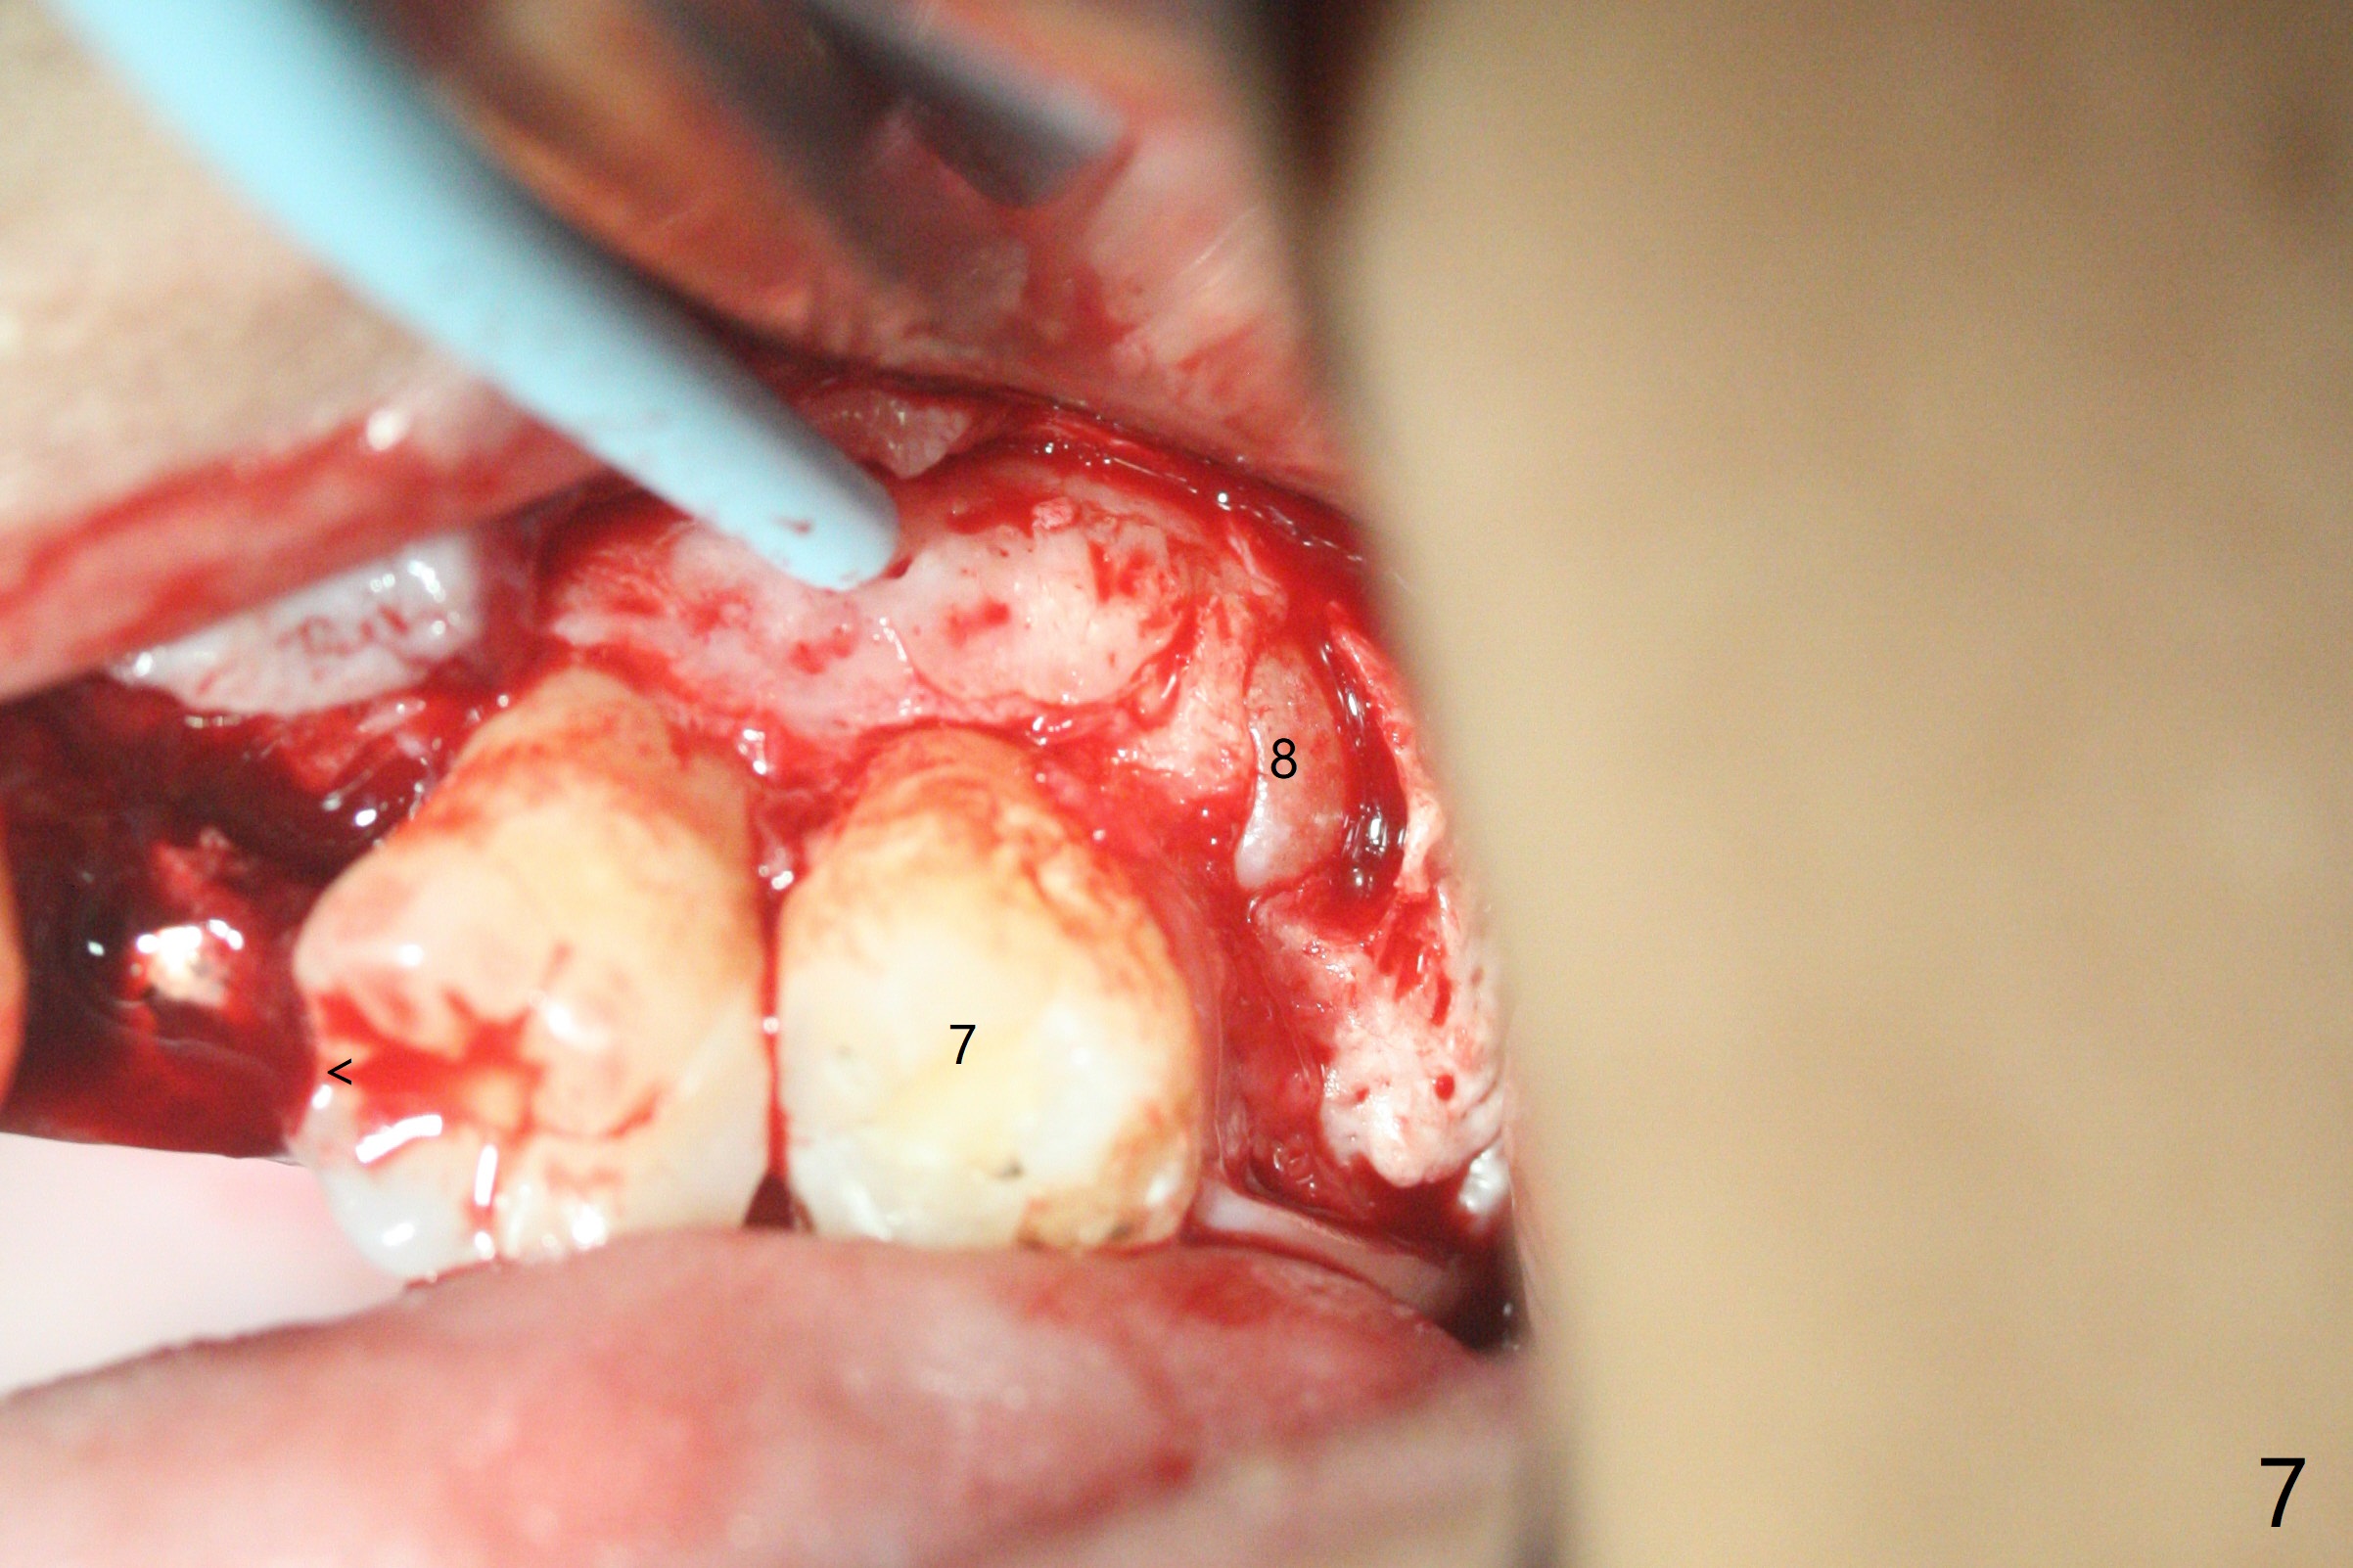

总之,左上8必须拔除(图七),其实必须两次手机切开才能去除。可能还需要拔除右上8,然后全口牙齿矫正。